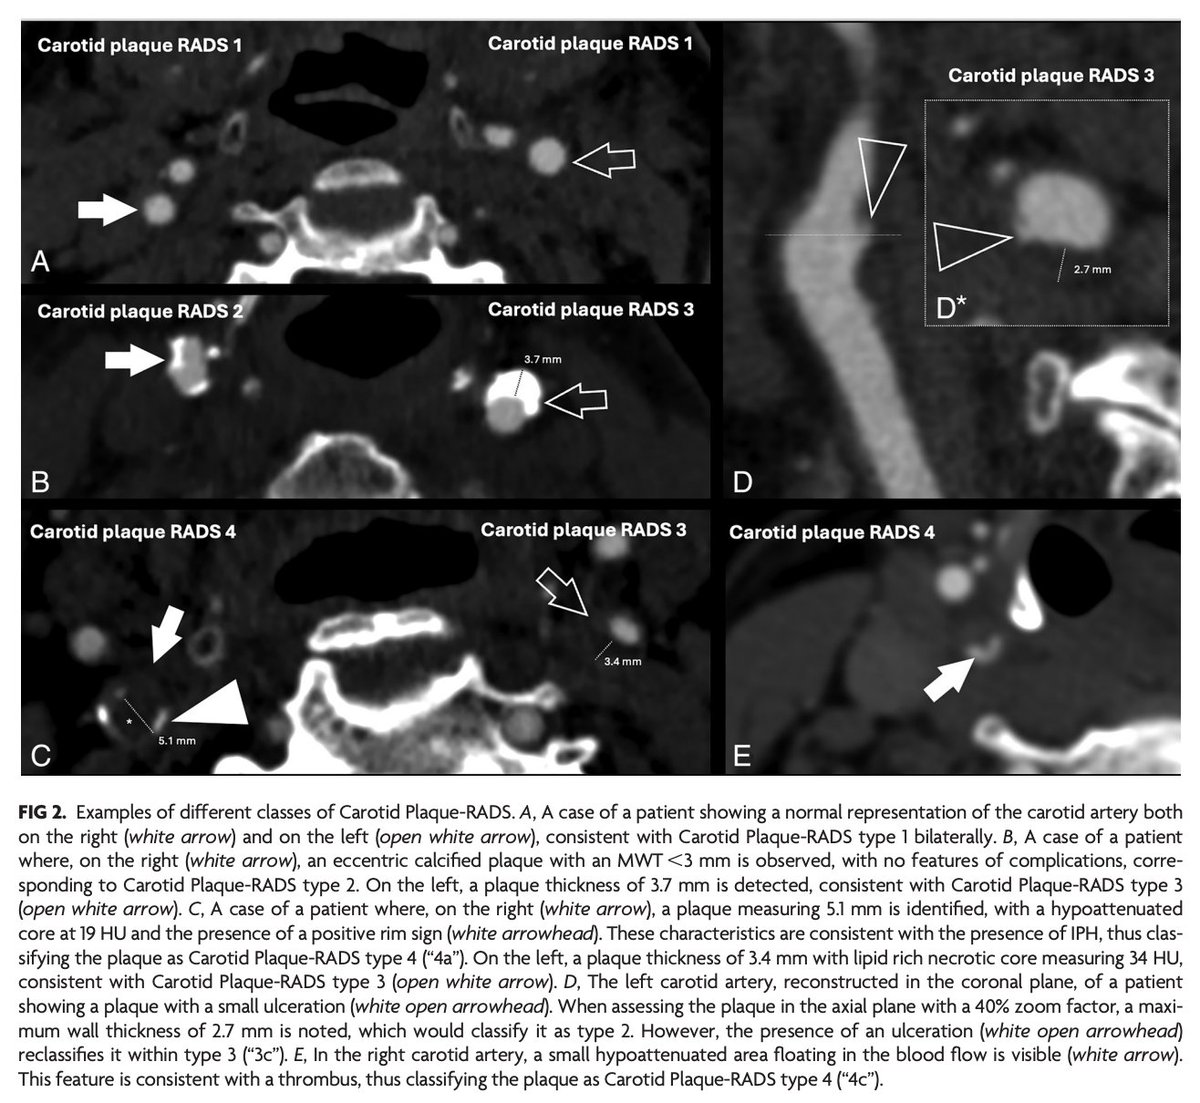

@lucasabaITA "The results of our study show that Carotid Plaque-RADS can be applied to CTA imaging with a very good degree of reproducibility among readers of different levels of experience. Further studies are needed to test the interreader agreement among readers with similar experience."

"Carotid Plaque-RADS: Inter- and Intrareader Agreement and Learning Curve Analysis in CTA" https://t.co/T8gTEnxO18

@lucasabaITA

2

24

63